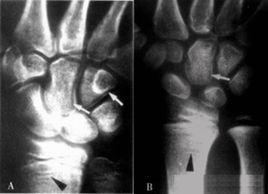

發作起來相當令人震撼的痛風,系因尿酸結晶沉積於關節腔液當中所致,病情嚴重時若透過肢骨X光攝影,則可於患者關節腔液中看到鈣化點。另一種假痛風(CPPD)則是因關節軟骨鈣化所引起之關節炎,在X光片中亦可看到軟骨鈣化的現象。這兩重鈣化點並不會出現在退化性關節炎患者身上。